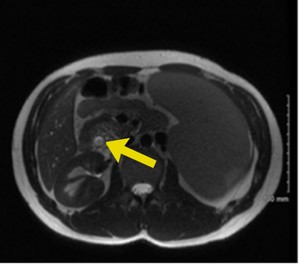

Right upper quadrant ultrasound revealed a distended gallbladder with cholelithiasis and no evidence of cholecystitis. Magnetic resonance cholangiopancreatography (MRCP) demonstrated biliary ductal dilation to 0.9 cm (reference range, 0.18 to 0.6 cm) (Figure 1), edematous pancreatitis, and splenomegaly to 22 cm (reference range, 12 to 14 cm) (Figure 2). Endoscopic retrograde cholangiopancreatography (ERCP) was notable for removal of a 5-mm pigmented stone, and laparoscopic cholecystectomy was performed without complications. Concurrent splenectomy with laparoscopic cholecystectomy was a consideration for this patient. However, given the patient's stable hemoglobin levels and recommendations that patients receive pneumonia, meningitis, and flu vaccinations at least two weeks prior to splenectomy, the procedure was deferred to be scheduled electively at outpatient follow-up.